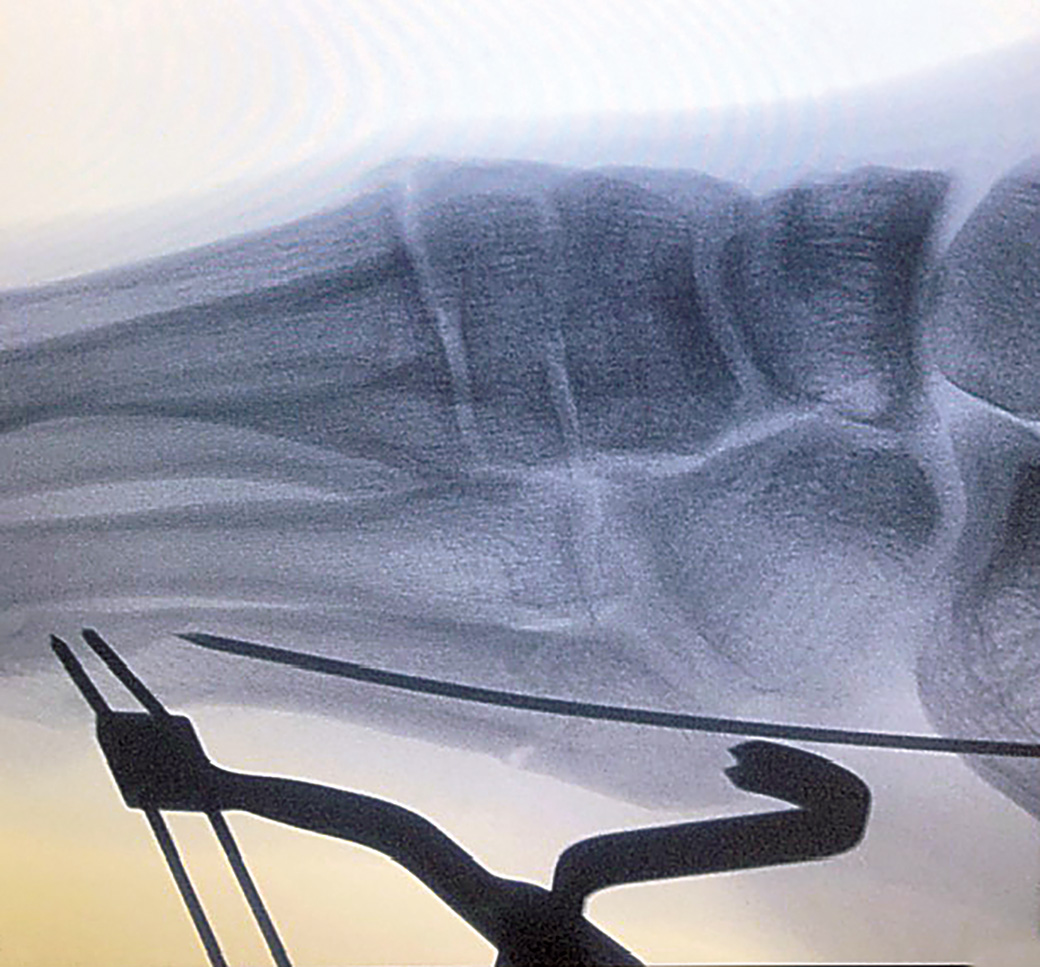

Designed to reduce and maintain reduction of Jones fractures, helping to prevent distraction and/or rotation during wire, tap, and subsequent screw placement

Distally there are two k-wire holes for placement in the distal 5th metatarsal and the 2-pronged clamp proximally is placed on the tuberosity, allowing a “high and inside” screw placement without interference.